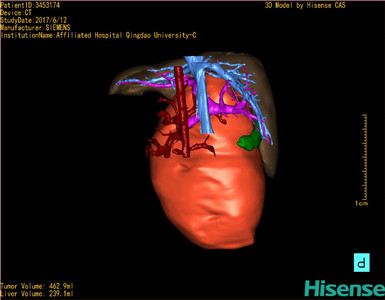

术前三维重建及手术方案设计:

将0.625mm双源薄层CT资料的静脉期和动脉期Dicom格式文件导入海信CAS系统。

通过调节窗宽窗位调整CT序号,对肝实质,胆囊,下腔静脉,肿瘤,肝动脉、门静脉及肝静脉等进行三维重建;系统自动计算肝脏体积。

模拟手术操作,自动计算切除肿瘤体积。肝脏体积为310.9ml,肿瘤体积为437.7ml,肿瘤体积是肝体积的1.4倍,通过比对9-12月正常肝脏体积为321.13±118.91ml,通过术前模拟手术,精准判断切除后剩余肝脏体积能耐受,避免肝衰竭发生。

麻醉成功后,患儿取平卧位,腰下垫枕,2.5%碘伏消毒手术区皮肤,铺无菌巾单。取上腹部人字形切口长约20cm,切开皮肤、皮下组织、肌层和腹膜。探查见肿瘤来源于肝中叶,约12×10×8cm大小,质地硬,肿瘤粘连压迫肝门部,与肝门静脉右支及左肝管粘连。逐渐分离切除肿瘤,肝门阻断后,完整切除肿瘤。仔细检查发现,肝门静脉右支有3处撕裂出血口,应用血管缝合线缝合修补。左肝管撕裂,应用可吸收线修补缝合。电刀肝创面止血后,肝针缝合压迫止血。放置腹腔引流管一根。检查无活动性出血,清点纱布器械无误,依次缝合腹壁各层。手术顺利,麻醉满意,出血不多,因术前贫血、血凝异常故术中输红细胞1U、冷沉淀80国际单位,术后病人先进入麻醉恢复室,苏醒后回病房。术后标本送病理检查。结果回示:肝中叶间叶性错构瘤。手术时手术者可开启Hisense CAS系统手势控制功能,对肿瘤的解剖结构进行实时、全方观察、评估,起到术中导航作用。

术前三维重建:

重建图片